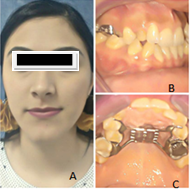

In both patients the same surgical technique was performed. Using the Hyrax as a distracter, anchoring the device to the first premolars and the first molars by orthodontic bands. Activation began on the sixth postoperative day and was carried out in an activation period by turning 2 times a day for 12 days. These procedures were performed on an outpatient basis with minimal morbidity, under general anesthesia with similar periods of time during activation in mm. of the hyrax, obtaining different symptoms and results by carrying out (Figure 3).7,8

Figure 3 Extra and intraoral photographs showing the initial condition of the patient and his distracting Hyrax type: See Maxillary Convergence. A,D: Extra and oral Frontal photo; B, C: Lateral Oral Photo; E: Photo with the Hyrax.

Figure 4 Patient with maxillary constriction, creating a pseudo class III. Undergoing the same procedure. A: frontal photo; B: lateral oral photo; C: oral photo with the hyrax.